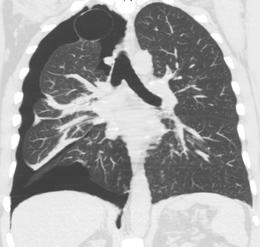

CT with the identification of underlying lung lesion: an apical bulla on the right side.

A CT scan is not necessary for the diagnosis of pneumothorax, but it can be useful in particular situations. In some lung diseases, especially emphysema, it is possible for abnormal lung areas such as bullae (large air-filled sacs) to have the same appearance as a pneumothorax on chest X-ray, and it may not be safe to apply any treatment before the distinction is made and before the exact location and size of the pneumothorax is determined.[14] In trauma, where it may not be possible to perform an upright film, chest radiography may miss up to a third of pneumothoraces, while CT remains very sensitive.[17]

A further use of CT is in the identification of underlying lung lesions. In presumed primary pneumothorax, it may help to identify blebs or cystic lesions (in anticipation of treatment, see below), and in secondary pneumothorax, it can help to identify most of the causes listed above.[14][18]